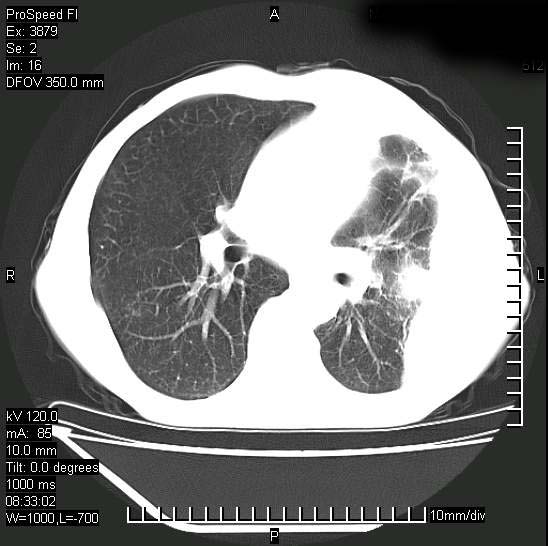

以下是引用312nanyang在2008-6-6 15:12:00的发言:[br]基本支持楼主意见[br]疑问?左下肺支气管旁的软组织(16层)密度怎么解释?淋巴结还是斜裂胸膜增厚所致?能否增强进一步检查